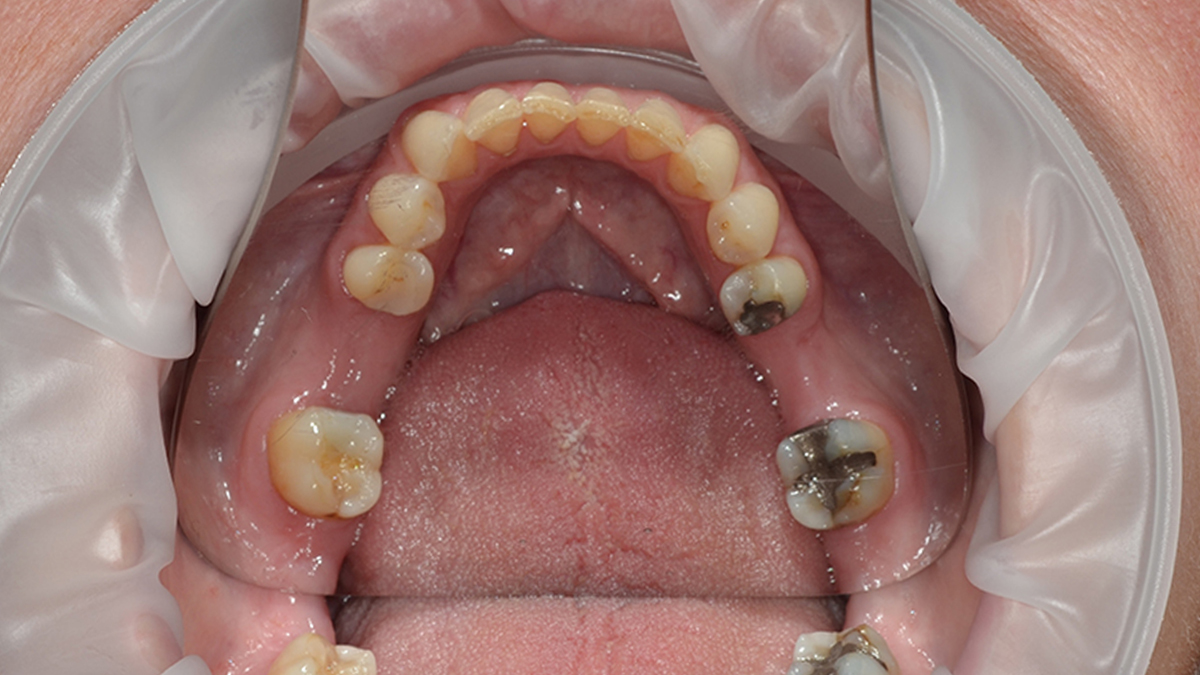

Általában ha a fognak csak egy kisebb része szuvas, a hiányzó rész kitisztítás után tömőanyaggal pótolható. A töméskészítést helyi érzéstelenítésben végezzük, egy alkalmat vesz igénybe. A tömőanyag egy speciális műanyag, kompozit, amely mind színében, mind fizikai tulajdonságaiban nagymértékben hasonlít a természetes foghoz, ezért alkalmas tartós és esztétikus tömések készítésére. Töméskészítés során a gyurmaszerű anyagot kis adagokban helyezzük az üregbe, majd az egyes rétegeket speciális lámpával világítjuk meg, melynek hatására megszilárdulnak. A tömés elkészültével az anyag kötése befejeződik, a fog terhelhető.

A tömőanyag tulajdonságaiból adódóan ma már, ha az üreg nem túl nagy, minden fogcsoport tömésére alkalmazható. Rágófogakban képes helyreállítani a funkciót, azaz egy erős, a rágóerőkkel szemben ellenálló tömés készíthető, frontfogakba (metszőfogak) pedig készülhet olyan esztétikus, észrevehetetlen tömés, mely kedvezően befolyásolhatja megjelenésünket, arckarakterünket.